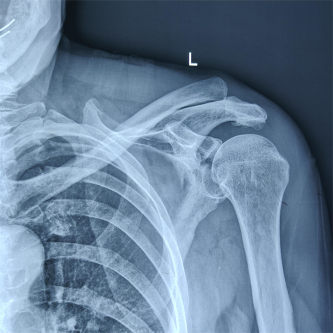

(术前X线及CT片)

患者因交通事故致伤导致左肩关节盂骨折及左肩锁关节脱位和右尺桡骨骨折,骨折移位明显,疼痛剧烈,具备手术指征。但患者为75岁高龄,基础疾病多,担心患者无法耐受过大的手术创伤。经术前讨论,创伤外科中心张立峰教授团队决定为患者应用骨科手术机器人辅助经皮内固定治疗肩关节盂骨折的手术方案。术中,通过机器人进行采集数据、并规划手术等人工智能操作,仅用1cm切口即成功完成手术。